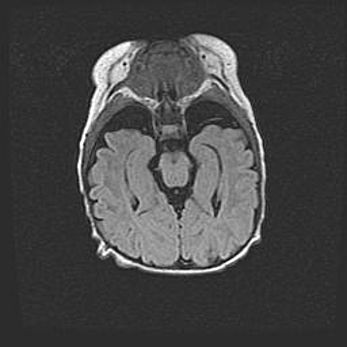

Наружная гидроцефалия с возможной атрофией височных областей.

Возраст: 28 дней

Вес: 3670 г

Пол: мужской

Окружность головы: 38 см

Срок гестации: 40 недель

Гидроцефалия головного мозга у новорожденных – это заболевание, которое характеризуется скоплением избыточного количества спинномозговой жидкости в желудочковой системе головного мозга в результате затруднения её перемещения от места выработки к месту поглощения в кровеносную систему или вследствие нарушения абсорбции. При открытой наружной форме гидроцефалии у новорожденных расширяются и переполняются субарахноидные пространства.

При нормотензивных  формах,  которые,  как  правило,  являются  следствием  перенесенных ишемических  повреждений  паренхимы  мозга,  возможно  сочетание микроцефалии  с нормотензивной гидроцефалией. В основе данных изменений лежит атрофия больших полушарий с преимущественной  локализацией  в  лобно-височных  областях.